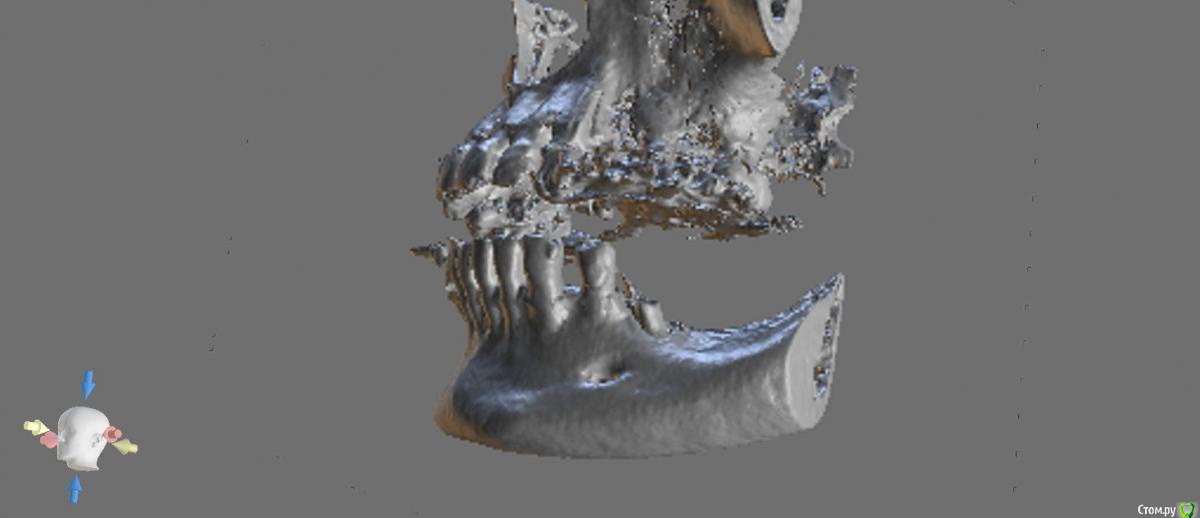

В 4м квадранте очень красиво стают штрауман коротышки TL. Но в позиции 6го много пломбировочной массы (остатки). не хотелось бы с таким ценником расширять показания: ставить близко к нерву, делать мост и тем более делать высокие коронки.

Скриншоты отображают самое главное, чтобы передать все нюансы надо смотреть КТ целиком... Сейчас голова уже не варит, завтра наделаю срезов ещё. Позиции имплантатов приблизительные.